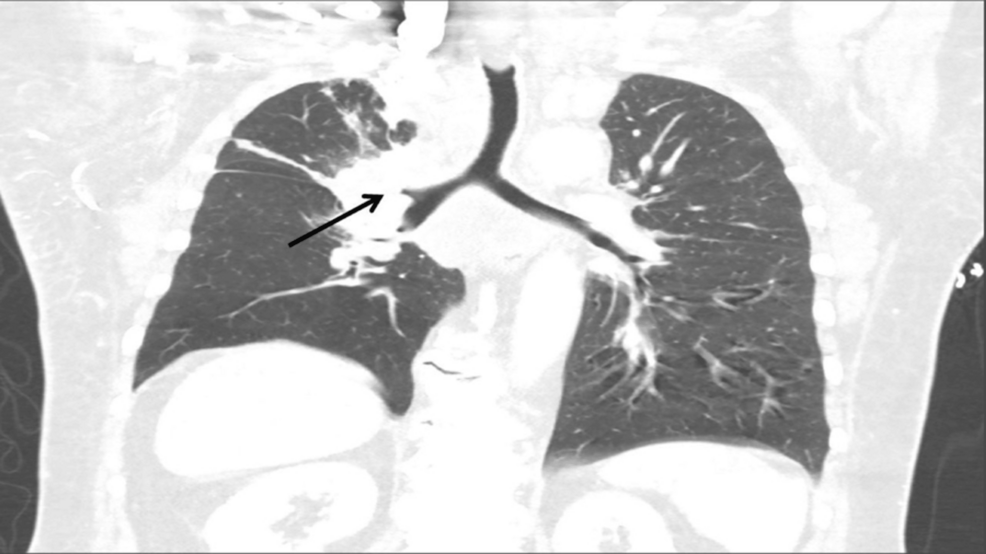

A 68-year-old obese white male patient (body mass index of 34 kg/m²) with a 50-pack-year smoking history presented to the emergency room with progressive anterior neck swelling, voice changes, and orthopnea that developed over three weeks. A chest computed tomography (CT) scan revealed a right hilar mass with direct extension into the mediastinum; the mass encased and nearly obliterated the SVC and right pulmonary artery and occluded the right upper lobe bronchus. The patient underwent balloon angioplasty of the brachiocephalic vein-SVC junction by vascular surgery under conscious sedation; however, due to involvement of the cavoatrial junction and the possibility of stent migration, they opted not to place a stent. He was started on inpatient radiation therapy and scheduled for a rigid bronchoscopy with biopsy by interventional pulmonology to obtain a histopathological diagnosis for a targeted treatment plan.